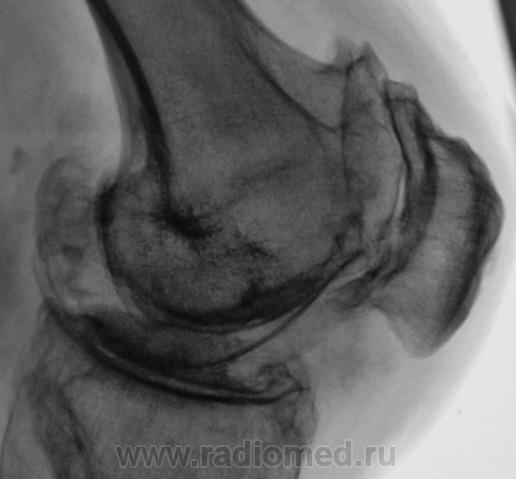

Боли в коленном суставе.

Деформирующий гонартроз 4 ст. или есть какой-то подвох? Двойной контур суставной поверхности медиального мыщелка бедра не Кениг ли случайно?

Не совсем точно выразиласьУлыбаюсь, не подвох, а что-то неординарное и заковыристое, например, манифестный ДОА в сочетании с чем-нибудь редко встречающимся.

я бы по коссинской 2-3 ст. деформирующего артроза написала, ито 3 ст это когда уже совсем не прослеживается суставной щели, а здесь она есть.

Согласен с DR.RAD двухсоронний гонартроз 2-3степени.

При второй стадии по классификации Н.С. Косинской, суставная щель-то должна быть сужена более чем на 50 %?

да а 3 стадия 2/3 как в данном случае...

Мне показалось, что суставная щель вовсе и не так уж сужена.А вот в пателло-феморальный суставе резкое сужение суставной щели.Выраженный субхондральный склероз, краевые остеофиты суставных поверхностей костей.А что там у Косинской по этому поводу написано, помните?

Н.С. Косинская - уже в прошлом (с уважением)... Понятно, что здесь первоочередным критерием являются деформирующие (обезображивающие)

остеофиты, а не ширина суставной щели; и суставные концы костей уплощены ("просели" за счёт остеопороза), и м/мыщелковые бугорки сглажены (бывшие остеофиты).

Оцениваем же в комплексе - все изменения.